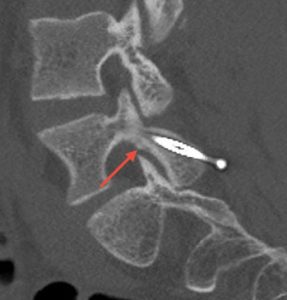

FM: Pars fracture repair is a very exciting area in spine surgery, particularly for younger patients and athletes, because it offers the ability to treat the source of pain while preserving motion. My focus has been on applying robotic technology to direct pars repair in carefully selected patients. As the highest-volume surgeon in New Jersey performing outpatient robotic pars repairs, I am currently studying my outcomes. We’re seeing that robotics can transform what was traditionally a more invasive procedure—often requiring 1-2 night hospital stays—into an outpatient surgery using small percutaneous incisions.

Patients are returning to sports as early as six to eight weeks post-operatively. While long-term comparative data is still evolving, robotics may improve reproducibility, shorten recovery, and maintain similar healing rates and long-term outcomes compared to traditional open techniques.

Images show pre-op CT and post-op CT, showing the healing, as well as a picture of the incisions. Image credits: Dr. Farah Musharbash